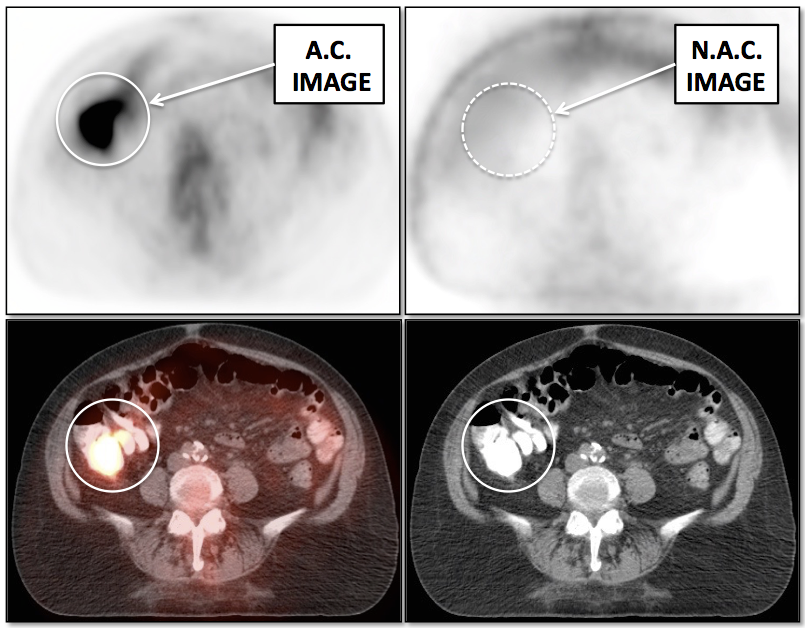

Value of Non-Attenuation Corrected (NAC) Images

Resolving Attenuation Correction Artifacts:

The CT images obtained during an exam are not only used for “anatomic” interpretation. They are also used for “attenuation correction” (AC) of the PET images, generating the much more useful AC PET images used for interpretation.

Unfortunately, attenuation correction of PET images can result in falsely elevated metabolic activity in regions of high CT density (e.g. metallic devices, oral contrast, calcification).

In such cases, these areas must be reviewed on the NAC (non-attenuation correction) images. If these regions are not also hypermetabolic on the NAC images, then their apparent increased FDG-uptake on the AC images is artefactual.

This phenomenon is almost exclusively seen with older PET/CT scanners, as most modern scanners utilize newer algorithms that do not “over-correct” in these areas of increased density.